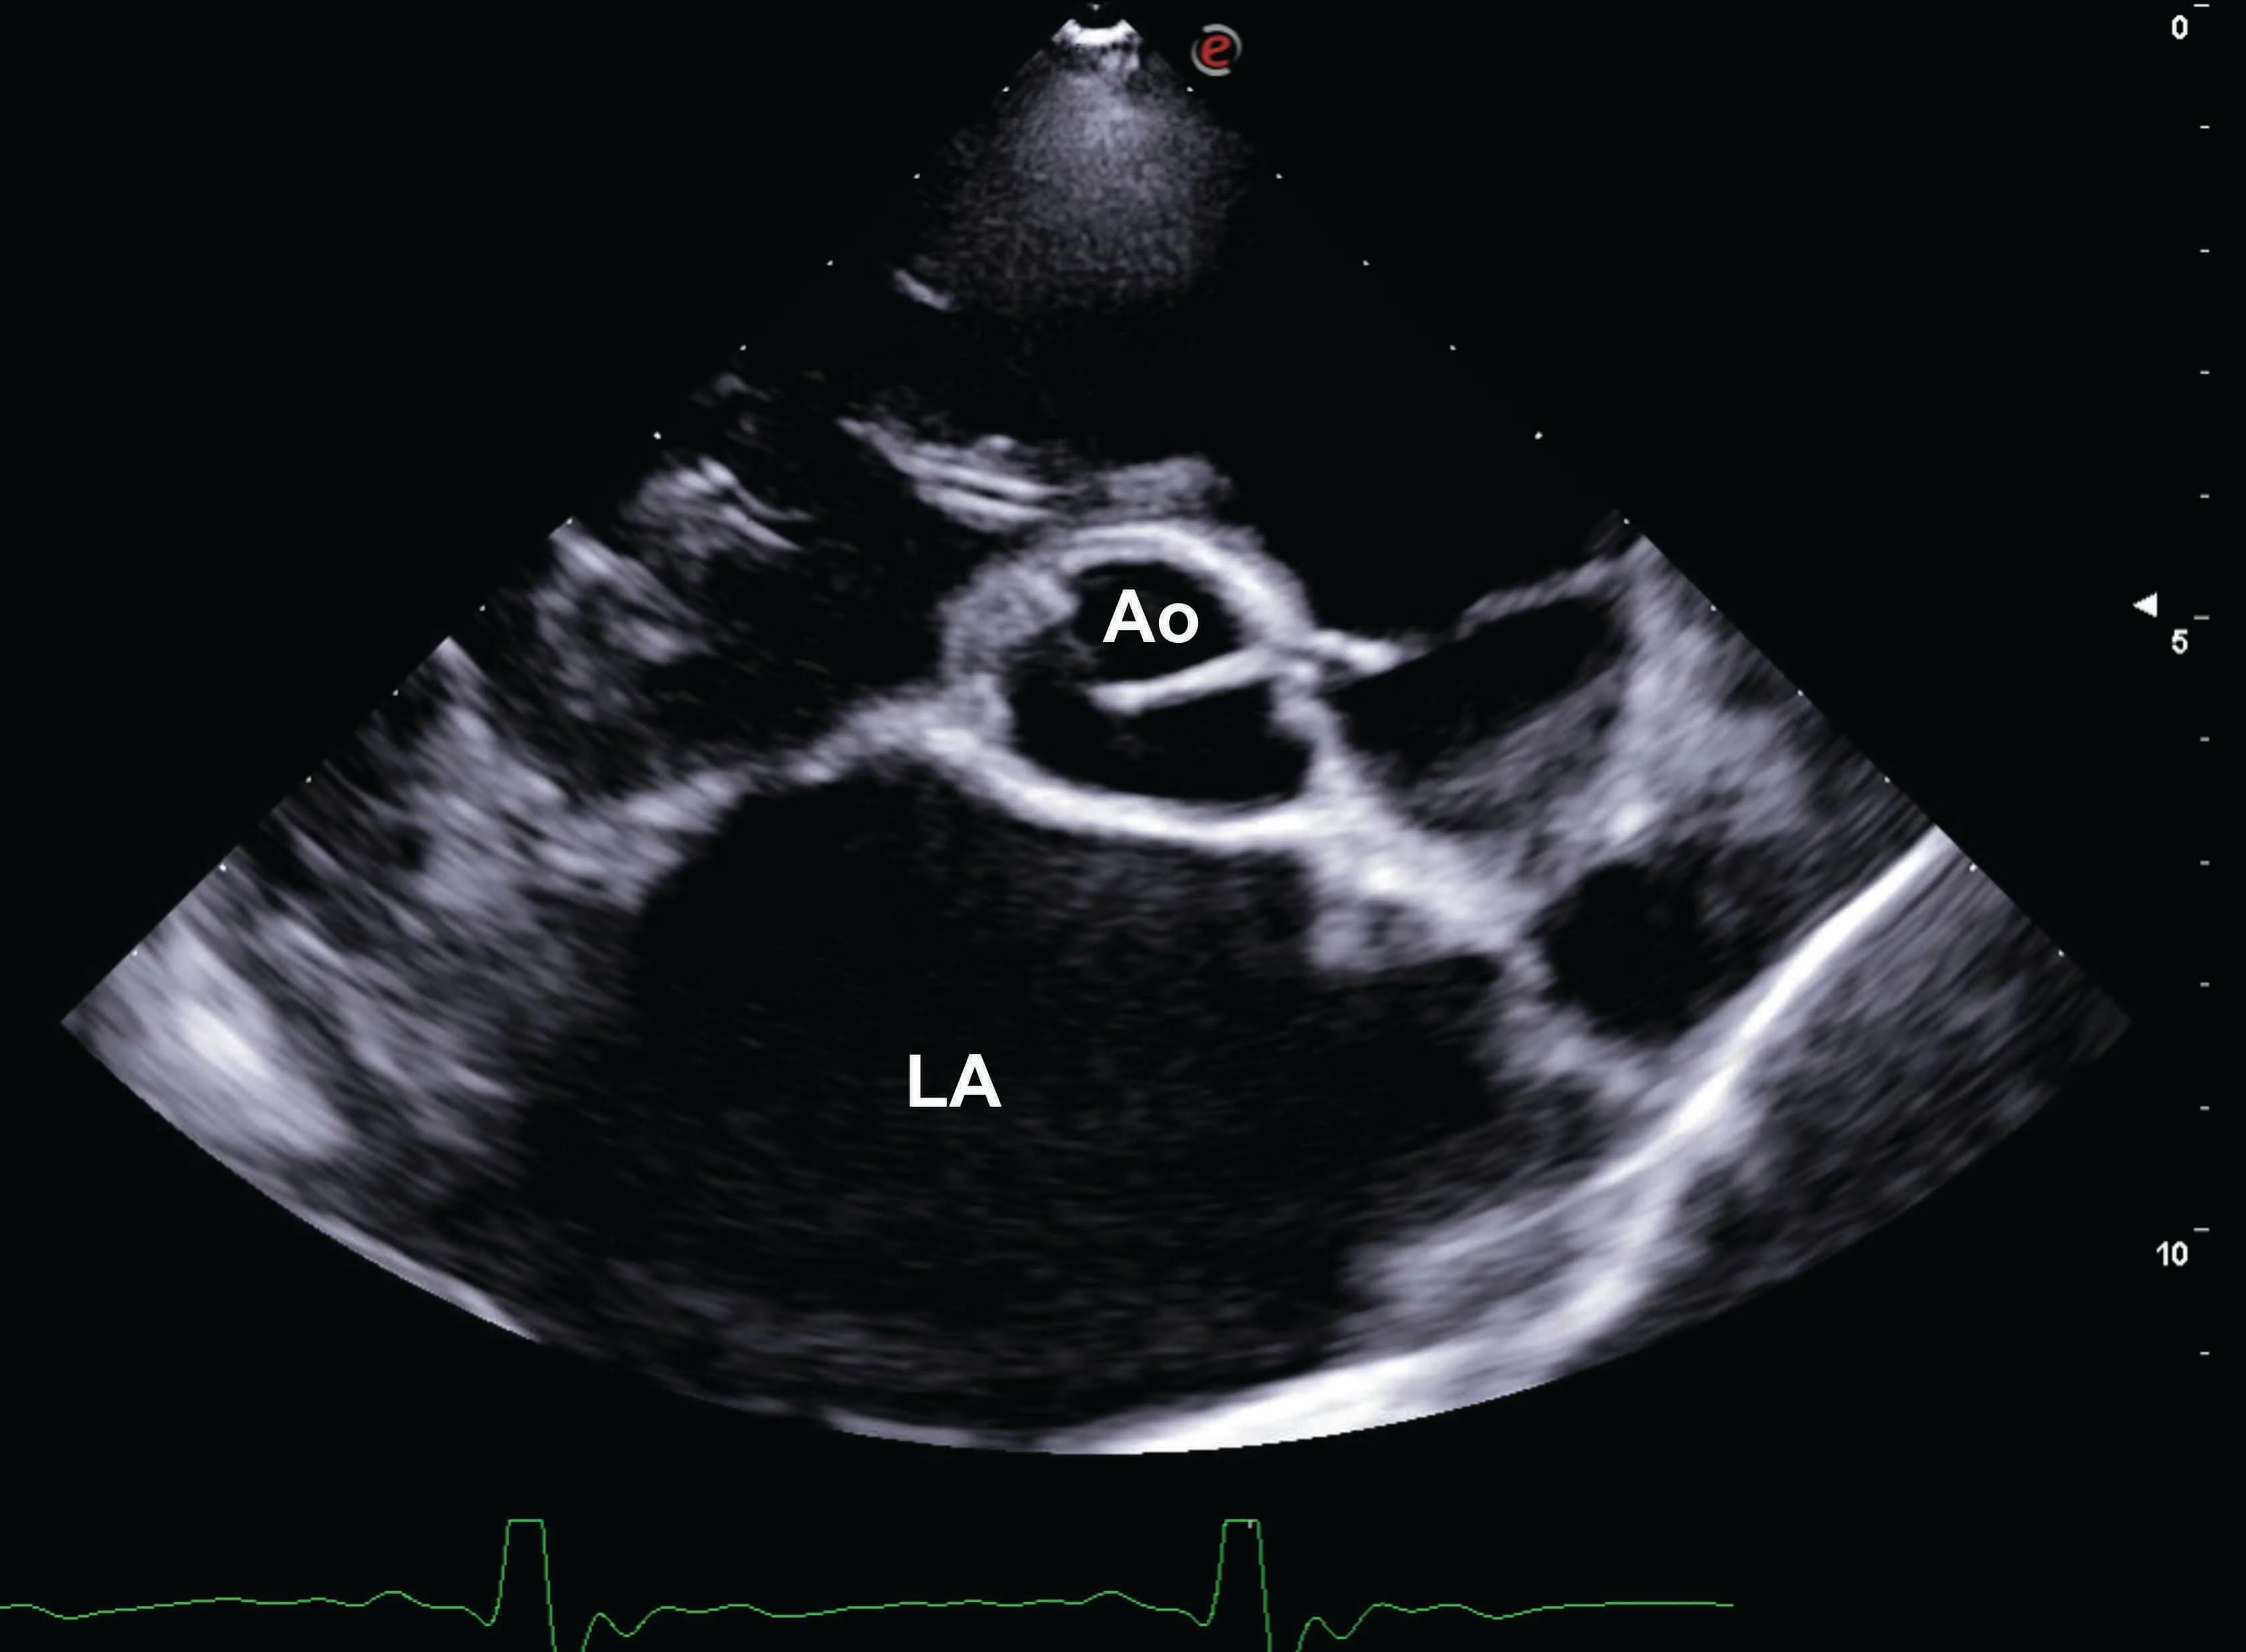

Heart failure in dogs is a serious medical condition where the heart cannot pump blood effectively to meet the body's needs. This can arise from various underlying causes, affecting different parts of the heart.

Classifications: Veterinary professionals categorize heart failure based on functional impact and the affected heart chamber.

Systolic Myocardial Failure: Problems with the heart muscle's ability to contract.

Pressure Overload: The heart works against high resistance.

Volume Overload: The heart must pump an excessive amount of blood.